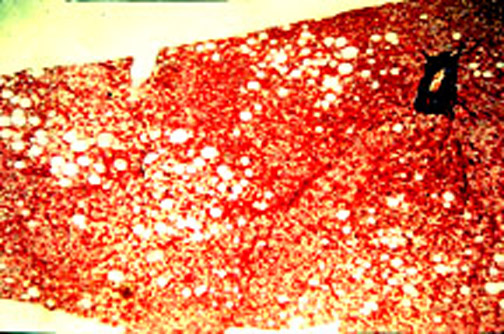

8-4-9.jpg (101480 bytes)

Fig. 8-4-9. Methotrexate hepatitis.

This is the earliest lesion. Thre are foci of  macrovesicular steatosis.